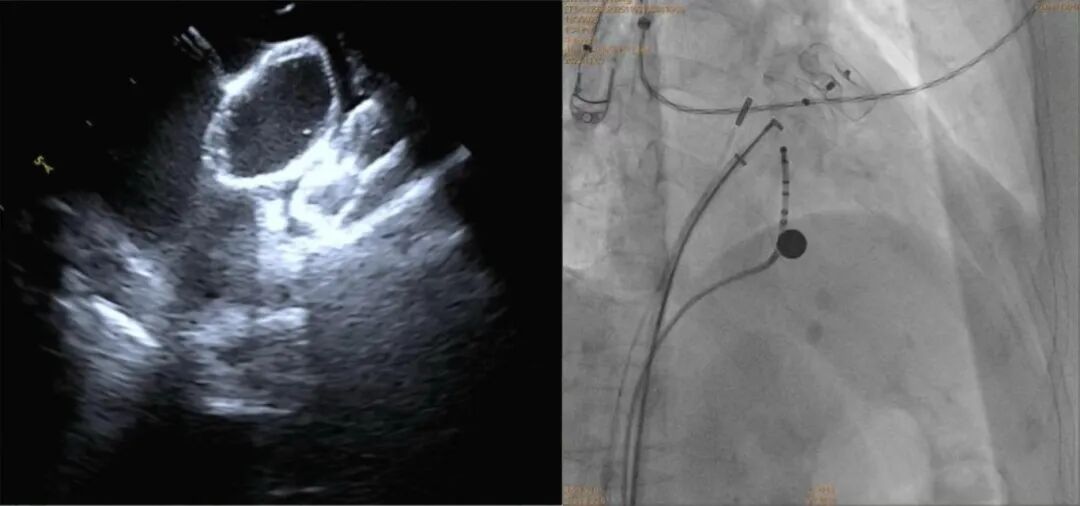

湖南省儿童医院成功开展全省首例儿童肺动脉高压PADN手术

锁骨与胸骨之后:一场在“透视盲区”完成的脊柱复位战